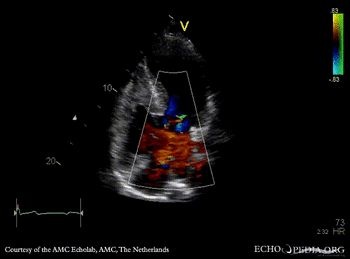

A4CH: Color Doppler signal of AVSD